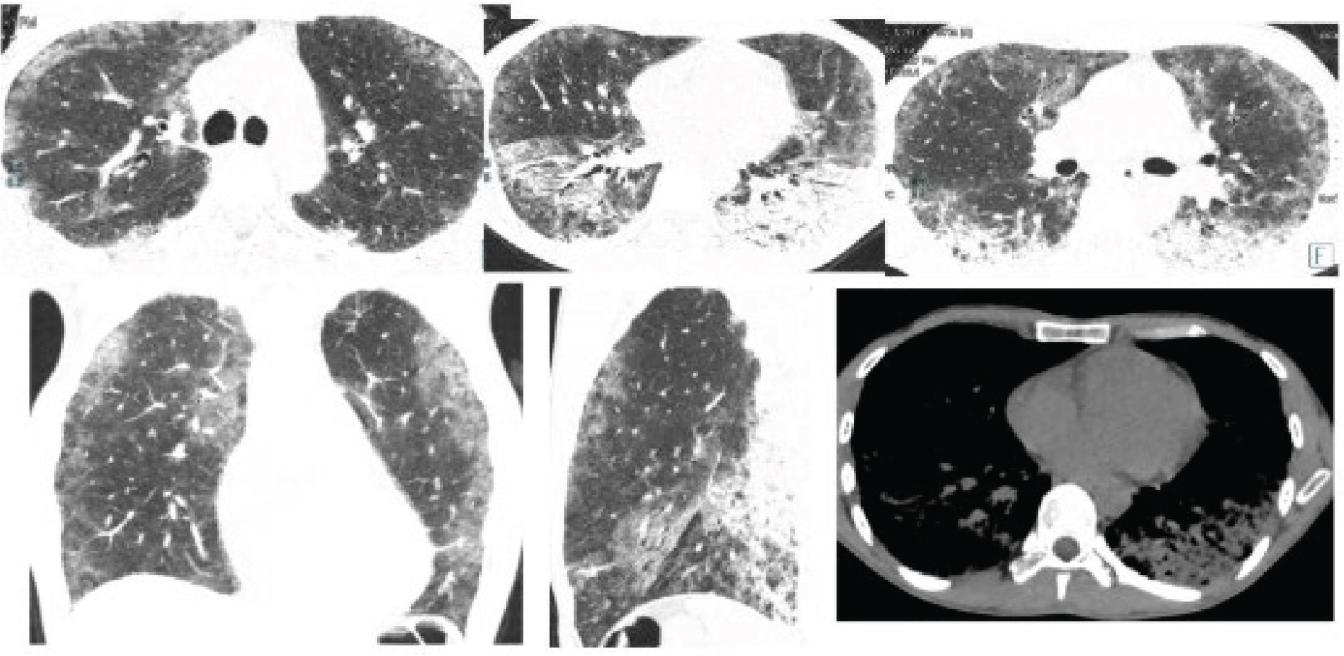

Chest computed tomography (CT) showed bilateral interstitial infiltrates with consolidations in the lower lobes, suggestive of atypical pneumonia (Figure 1). He was started on intravenous levofloxacin with nasal oxygen. The patient’s temperature normalised within 24 hr and he was successfully weaned from supplemental oxygen. He was discharged with oral levofloxacin 500 mg once daily to complete the 7-day antibiotic course.

High-resolution CT images show patchy subpleural ground-glass opacities throughout both lungs and alveolar consolidations in both lower lobes. CT, computed tomography.